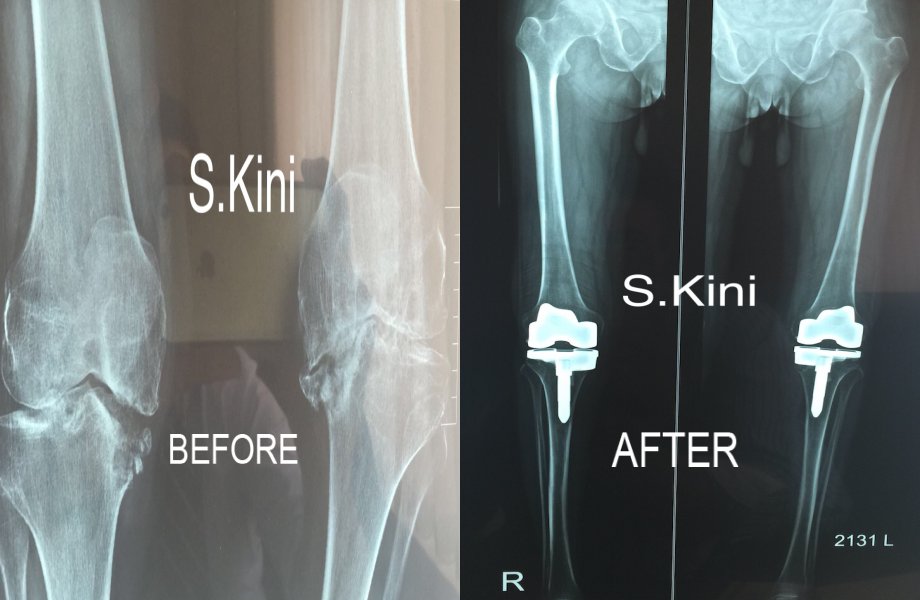

Total Knee Replacement